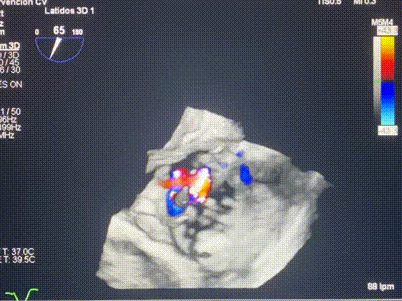

術(shù)中輸送器在超聲引導(dǎo)下調(diào)整位置

手術(shù)在全麻狀態(tài)下進(jìn)行。術(shù)者采用經(jīng)右側(cè)頸靜脈入路的方式將輸送器送入患者心臟內(nèi),在TEE及DSA引導(dǎo)下調(diào)整輸送器頭端角度,使得輸送器與三尖瓣瓣環(huán)平面垂直。在輸送器進(jìn)入右心室后釋放室間隔錨定裝置,而后釋放瓣葉夾持件(2個(gè)耳片結(jié)構(gòu))成垂直狀態(tài)。在TEE及DSA確定夾持件固定至三尖瓣葉根部且位于右室側(cè)后釋放人工瓣心房側(cè)盤片。隨后調(diào)整瓣膜同軸性以及室間隔錨定件位置(貼合室間隔),前推藏針管并固定,進(jìn)而釋放室間隔錨定裝置,并再次確認(rèn)瓣膜位置、穩(wěn)定性及同軸性,合攏輸送鞘后撤出輸送器,完成LuX-Valve Plus人工三尖瓣瓣膜的植入,僅殘余微量瓣周漏。且經(jīng)手術(shù)中心電生理團(tuán)隊(duì)評(píng)估,病人的起搏器和ICD功能沒(méi)有受到影響。